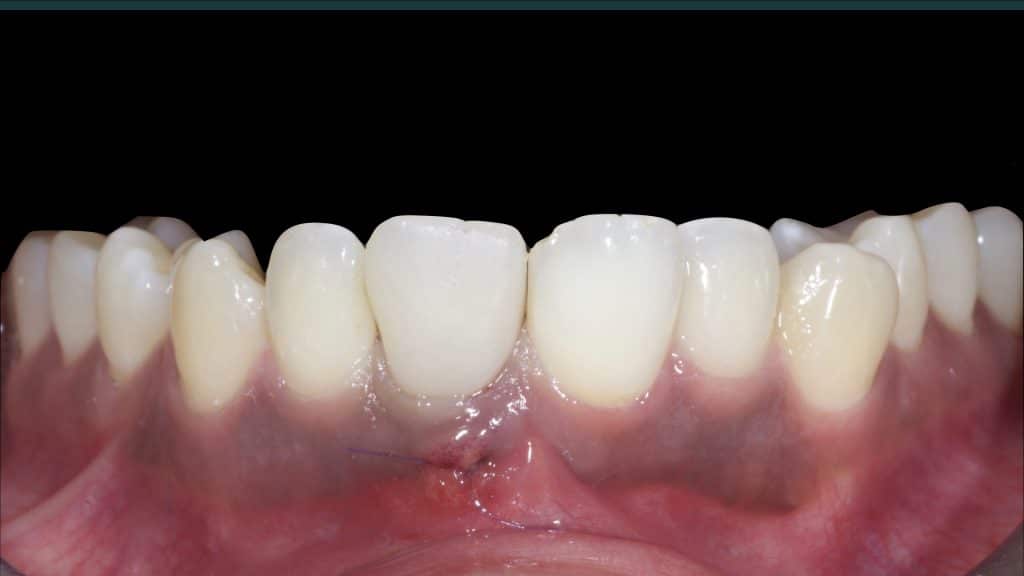

20 days post-op after suture removal